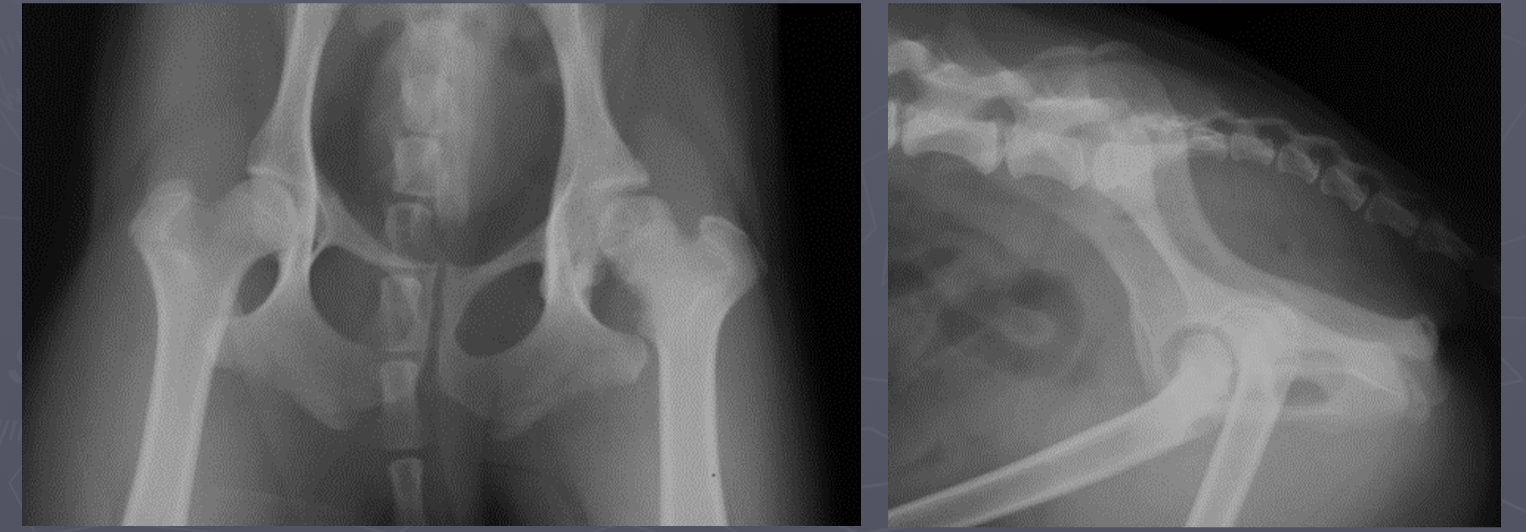

hip dysplasia signalment

large breed dogs

bilateral - inherited

flattened acetabulum, bad femoral head coverage, osteophytes along rim, morgans line

hip dysplasia

morgans line - early sign of DJD

what are the 3 views PennHip wants for hip dysplasia

extended leg VD

compression VD

distraction VD